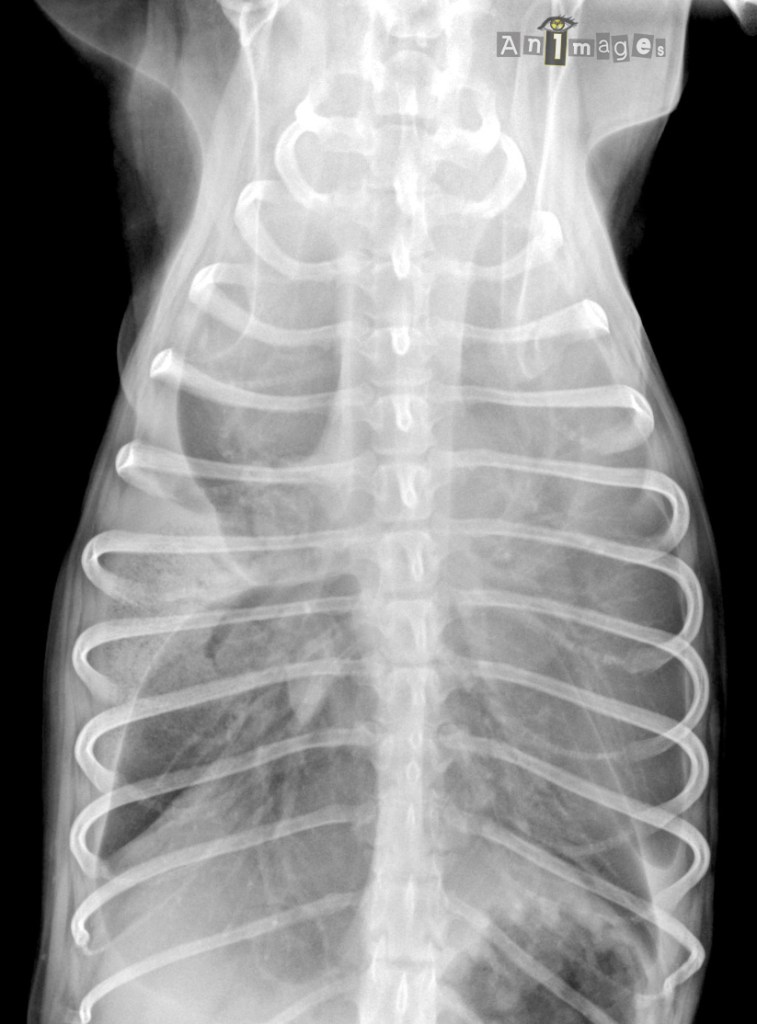

dorsoventrale